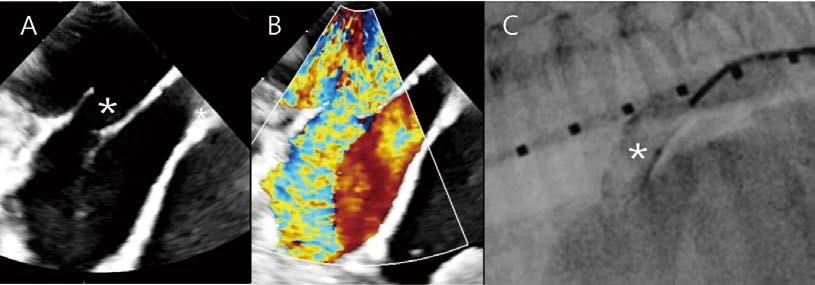

이 환자 역시 PDA, L to R 환자입니다. 경흉부심초음파에서는 canine PDA angiographic classification 을 바탕으로 type 2A로 생각되었으나, 실제 경식도심초음파(A, B)와 혈관조영술 모두에서 Type 3(ductus 직경의 실질적인 감소(<20%)가 없는 tubular 형태)로 확인되었습니다. PDA occluder failure 위험도가 높아 surgical ligation을 실시하였고, any complications 없이 치료를 종료하였습니다.

Catheter based occlusion 시술에서 반드시 필요한 것은 아니지만, 경식도심초음파를 이용하게 되면, 보다 세밀한 정보를 실시간으로 얻을 수 있습니다. 다음 환자에서도 경식도심초음파를 통해 PDA type및 직경 평가(A), 카테터 진입 및 적절한 위치 평가(B, 붉은 화살표), 실시간 혈류 평가(A, 시술 전, C duct , occluder 장착 후), duct occluder의 정확한 위치 및 안정성 평가(D, E 파란 화살표) 등의 세밀한 정보를 catheter based occlusion 시술과 동시에 실시간으로 얻을 수 있었습니다.